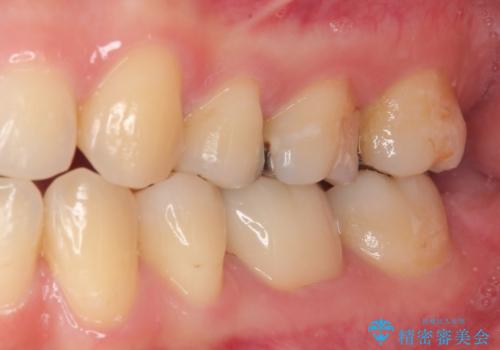

銀歯のところがしみる オールセラミッククラウン

- 左下の銀歯のところがしみるとのことで来院された患者様です。

レントゲン上で金属の詰め物(メタルインレー)の下に虫歯を認めました。